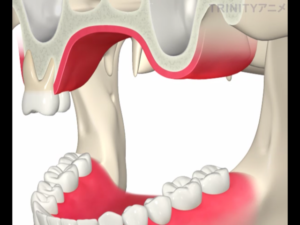

上顎の上方には副鼻腔(上顎洞)と呼ばれる、鼻とつながる空洞が存在します。

下の赤線で囲まれた部分です。

この部分にインプラントが飛び出してしまうと鼻に炎症を起こす可能性があるため、その下の骨の内部で留める必要があります。

今回の画像をみるとわかりますが、骨が極端に少ない状態です。

下の図のように上顎の骨が少なく、副鼻腔との距離が近く骨を盛り上げる場合に選択する治療方法です。

歯茎を切開し、副鼻腔につながる骨を一部削除します。

副鼻腔内の粘膜を破らないように慎重に上方に持ち上げていきます。

それによってできた副鼻腔内の空洞に人工骨を填入します。

骨を盛り上げた部分にインプラントを埋入します。